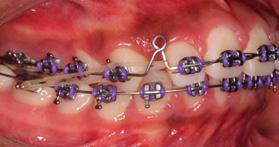

Toma, medición y montaje de modelos de trabajo (Figura 2). En oclusión céntrica se obtiene una sobremordida horizontal positiva de 1 mm con una relación molar clase I. Se confeccionó el arco con un calibre con alambre TMA 0.032 impreso sobre las caras palatinas de los dientes 11 (>) y 21 en el modelo, con el objetivo de ejercer un movimiento de vertical anterior de 2.5 mm sobre los dientes ya en boca. Se colocaron módulos de separadores interdentales y se aplicó flúor. En la cita de inicio de tratamiento, se cementaron las bandas ya con las cajas palatinas soldadas sobre las cuales se posiciono el arco de alambre TMA calibre 32; hay que recordar que es obligatorio

pulir cuidadosamente las puntas del alambre TMA, dejándolas romas para evitar irritación en la lengua de los pacientes, común en pediátricos, así como el adosamiento y calibración de las bandas. Se descansó sobre las caras palatinas el alambre del arco a 3 mm del cíngulo de los dientes 11 y 21, fijándose con alambre número 8, entorchado, sujetando con amarre firme, circunscrito a la corona de los dientes 54 y 64, cuidando de no provocar movilidad, avulsión o situación periodontal negativa (Figura 3), recordando que los omegas de los arcos deben de quedar separados de la mucosa de 1 a 2 mm después de ser ligados para no lesionar la encía.

palatina para generar la rotasión y protrución del diente 21, así como del 11 en su momento. El control a las 2 semanas demostró el acomodo correcto de los dientes centrales superiores, propiciando el avance deseado y los contactos apropiados entre los bordes incísales (Figura 4). Se mantuvo el aparato una semana posterior, con evaluación cada 72 horas para el sostenimiento del movimiento logrado. No hubo modificación o alteración de la clase I molar, tampoco en el ancho intermolar e intercanino superior, siendo que la corrección de la mordida cruzada vestibular se realizó a expensas de modificaciones anatómicas dentarias solamente. A pesar de la colocación del amarre con el alambre entorchado, tampoco hubo movilidad de los deciduos o alteración de su periodonto.